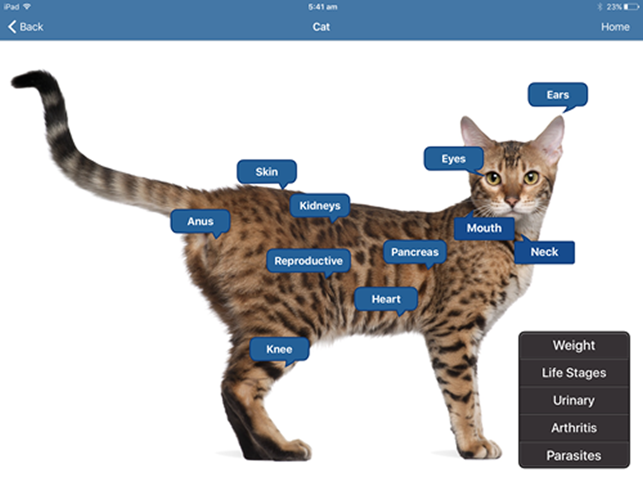

The iConsult application is a veterinary application designed for use in the consultation room AND reception, but that's not all. You can also use it to target market your clients using the e-books within the ap, use it as a tool to win over new clients and convert phone shoppers too!

Educate your client effectively

Increase value to your services